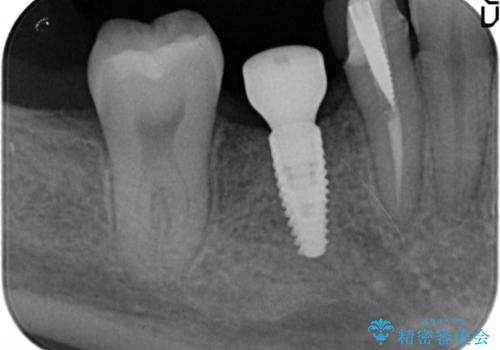

インプラント治療をご希望されたため、植立を行いました。

インプラントを入れる際、部分的に骨を増やす処置を行っています。